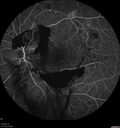

44 year old man About 2 months ago, the patient went to the beach with his family and noticed a hair in the eye sight in the left eye.  He was trying to rinse it out and saw that there was something not right.  He googled the problem and there was something about a floater and not being a big deal.  His vision was pretty good.  He was not getting regular eye examinations.  He did get checked in 2015 and got new glasses.  He had not been back since then for the last 5 years except for glasses. Last week the vision in the left eye got bad.  The vision in the right eye is fine.   VA OD: sc20/40 PH20/25 NscJ2 VA OS: sc20/63-2 PH20/32-1 NscJ1 IOP: TP: OD:17 OS:19

Proliferative Diabetic Retinopathy and vitreous hemorrhage left eye330 views44 year old man with type II diabetes for 14 years and no eye examinations in the last 5 years. VA 20/40 right eye and 20/60 left eye. Vision loss has been for about a week in the left eye.00000

44 year old man About 2 months ago, the patient went to the beach with his family and noticed a hair in the eye sight in the left eye.  He was trying to rinse it out and saw that there was something not right.  He googled the problem and there was something about a floater and not being a big deal.  His vision was pretty good.  He was not getting regular eye examinations.  He did get checked in 2015 and got new glasses.  He had not been back since then for the last 5 years except for glasses. Last week the vision in the left eye got bad.  The vision in the right eye is fine.   VA OD: sc20/40 PH20/25 NscJ2 VA OS: sc20/63-2 PH20/32-1 NscJ1 IOP: TP: OD:17 OS:19Â